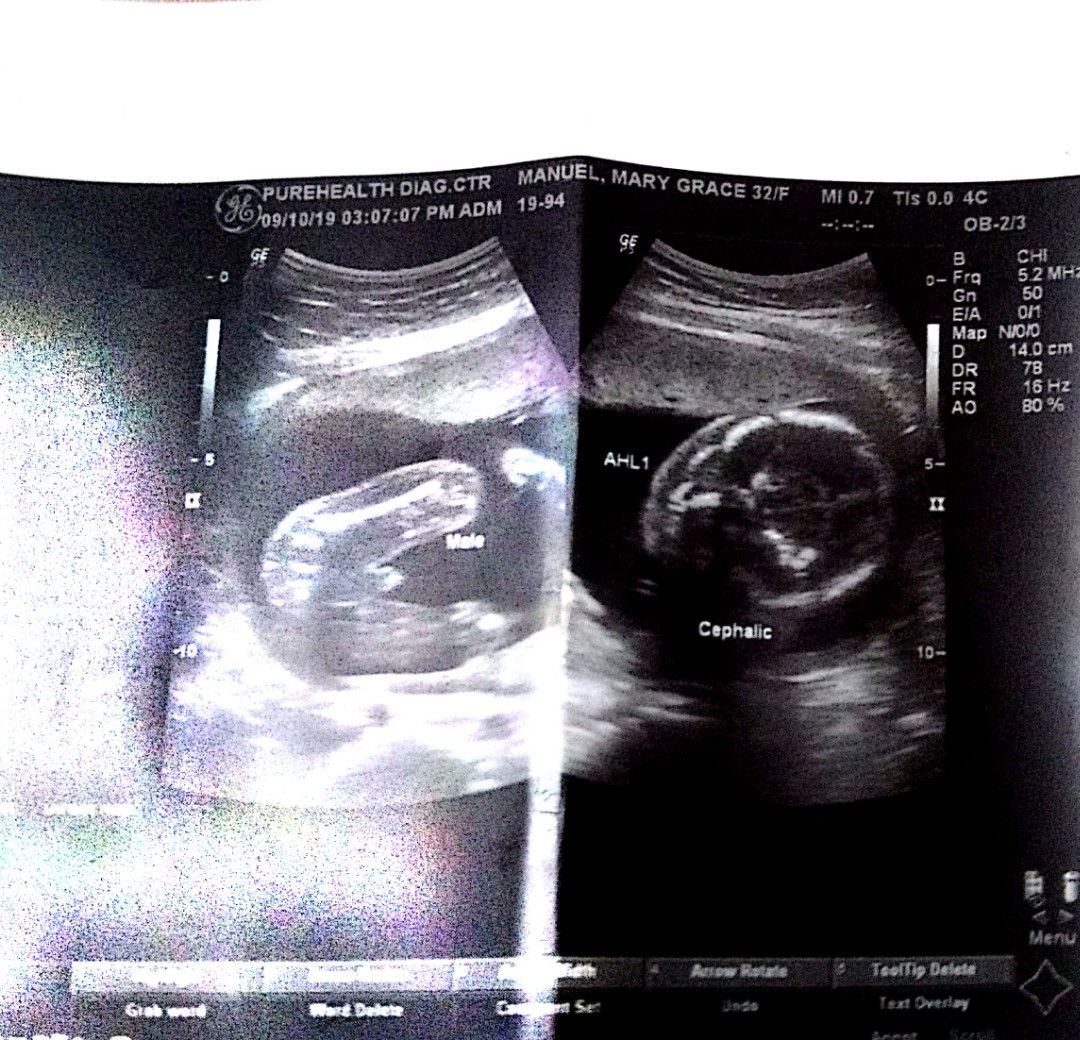

Ask q lan poh..ngpa ultrasound kz aq ngaung 5 mos..nkita sa ultrasound male...zbi ng iba pg mxado dw maaga ng pa ultrasound..mnzan d pa dw un sure...22o kaya un?guz2 q na kz mamili ng mga dmit ni bby..salamat poh sa mkakapansin

Sure na po yan gender ni baby kc may lawit. Pag girl naman flat na parang burger..

sure na lalake po yan😁 my lawit..

lalake talaga.